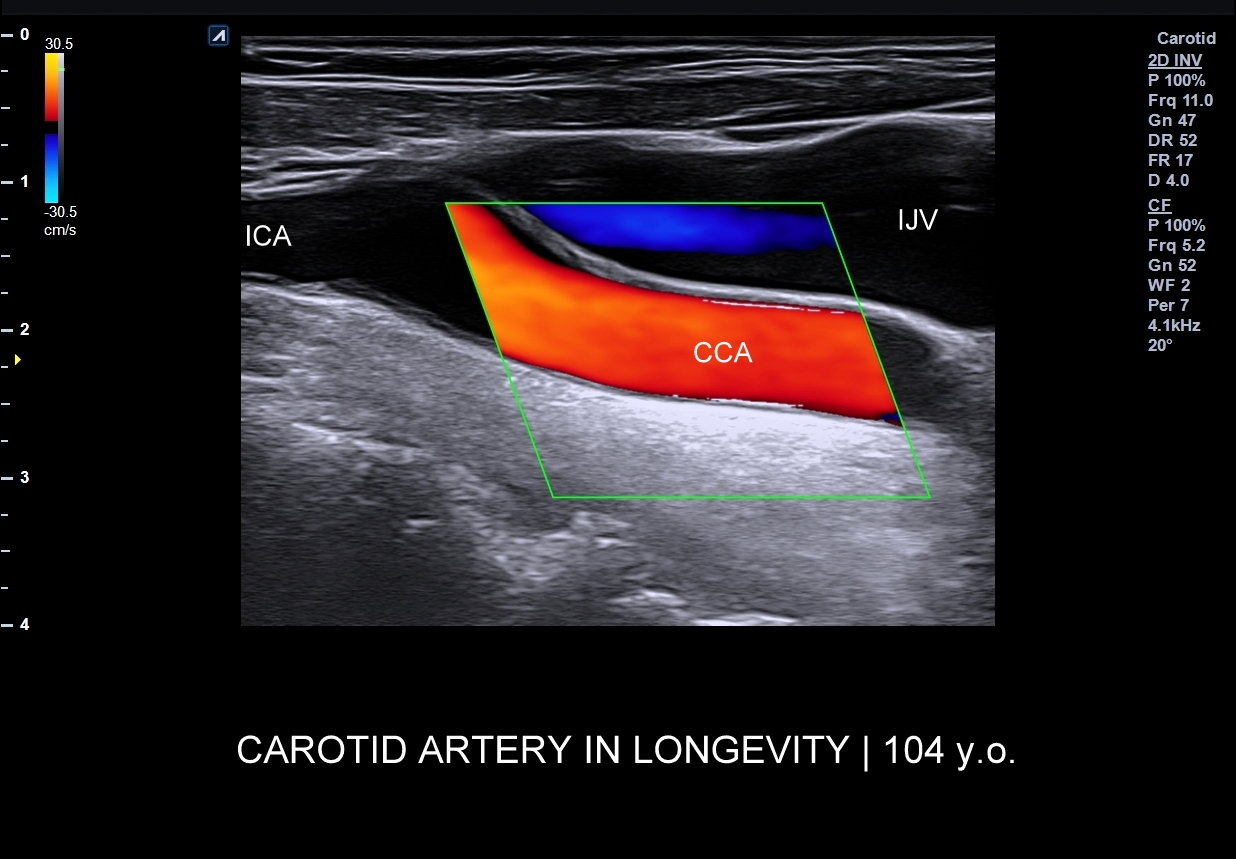

- LONGEVITY | TĘTNICE JAKO NARZĄDY WARUNKUJĄCE DŁUGOWIECZNOŚĆ.

Dzień poświęcony tętnicom w ramach Kursu USG Doppler Cedum ® umożliwi poznanie tajników badania dopplerowskiego tętnic dogłowowych, tj. szyjnych i kręgowych; jednej z najważniejszych naczyniowych metod diagnostycznych wykorzystywanych w różnorodnych dziedzinach medycyny, w tym w chirurgii naczyniowej, kardiochirurgii, angiologii, kardiologii, czy neurologii. Badanie Doppler tętnic dogłowowych przeprowadza się m.in. w trakcie diagnostyki zawrotów głowy, omdleń, udarów mózgowych i TIA, a także w ramach procedur przygotowawczych przed poważnymi operacjami, np. kardiochirurgicznymi. Wykorzystuje się je również w przesiewowej ocenie stanu układu sercowo-naczyniowego. W trakcie interdyscyplinarnego Kursu USG Doppler Cedum ® omawiane są m.in. technika i kompleksowe cele badania tętnic szyjnych, kręgowych, a także podobojczykowych, łuku aorty oraz tętnic wewnątrzmózgowych; hemodynamika układu tętniczego w fizjologii i w stanach patologicznych, takich jak zwężenia, niedrożności, czy zespoły podkradania.